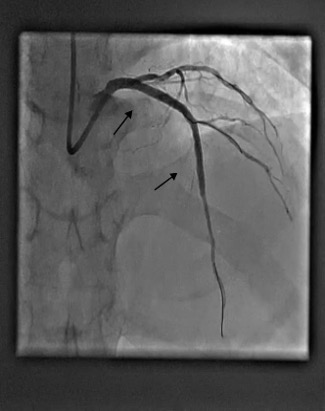

A 72-year-old male underwent elective percutaneous coronary intervention (PCI) for a significant stenotic lesion in the left anterior descending (LAD) artery (Figure 1 white arrow, Video 1).

A wire was placed in the diagonal branch prophylactically to preserve side branch patency during main vessel stenting. After successful deployment of a drug-eluting stent (DES) in the LAD, the side branch wire was withdrawn. However, a radiopaque segment remained within the side branch, while the remaining wire fractured and became entrapped behind the stent struts (Figure 2 [black arrows], Video 2).